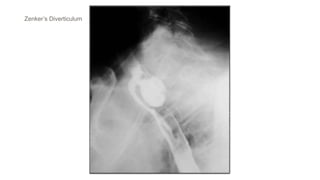

Zenker’s Diverticulum